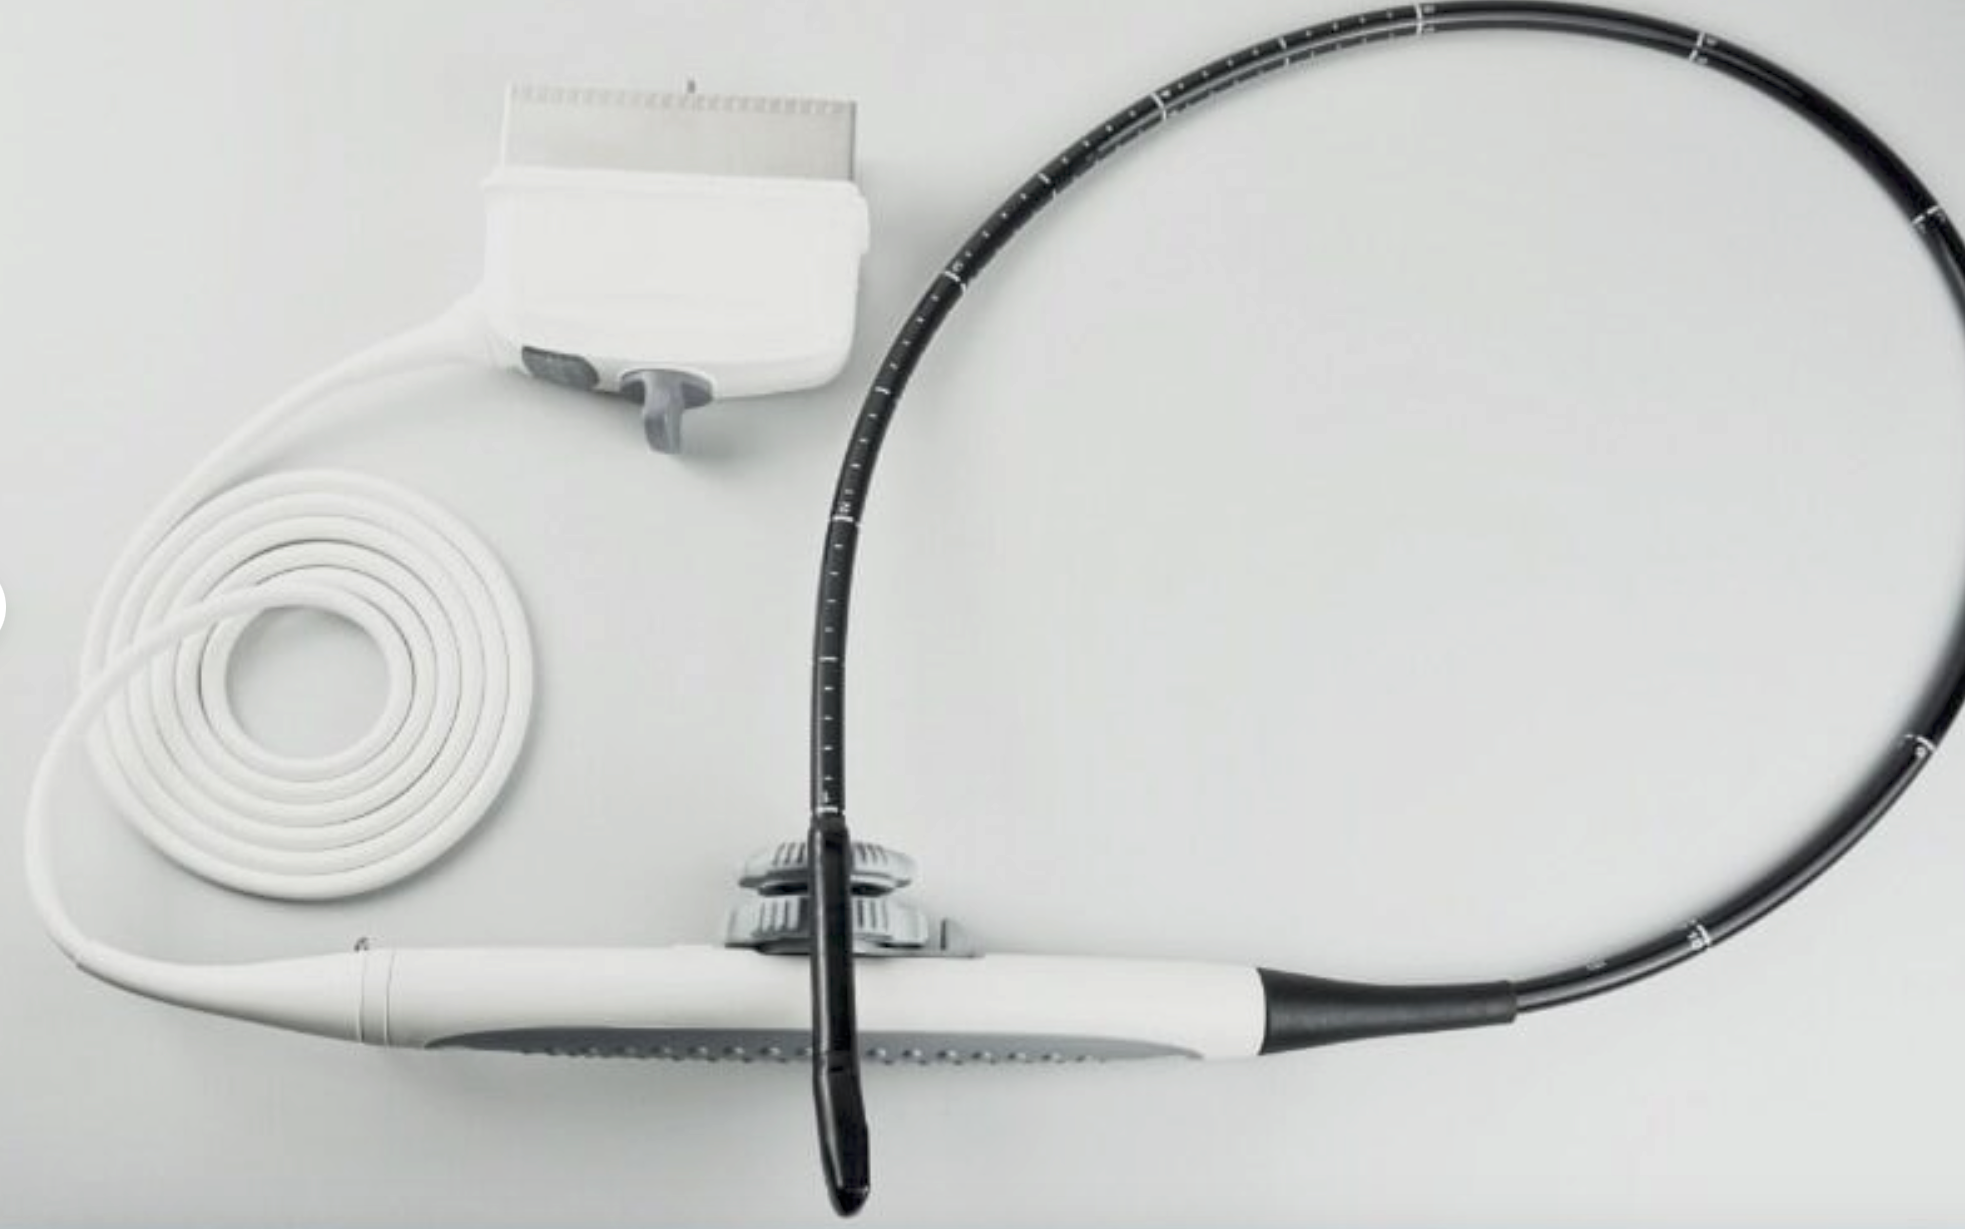

Optional: 3.5MHz R60 convex probe

7.5MHz linear probe: 6.5MHz Trans-vaginal probe

5.0MHz Micro-convex probe: Video Printer Sony UP-897